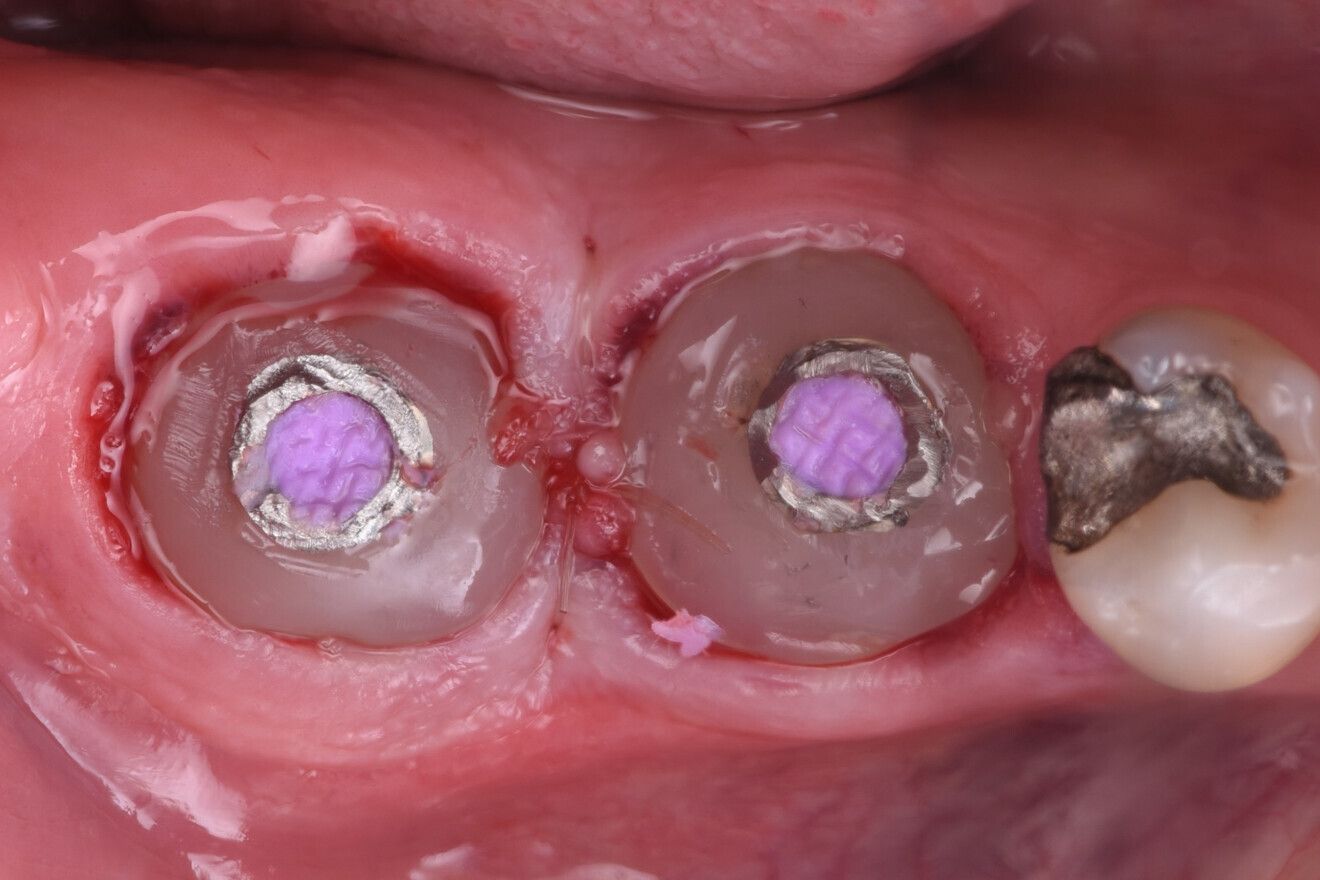

The implants (5 × 9 mm CONELOG PROGRESSIVE-LINE, BioHorizons Camlog) were then placed using the sleeveless surgical guide and the CONELOG guided kit (Figs. 9 & 10).

After verification of the implant placement, the grafting material (MinerOss Putty allograft, BioHorizons Camlog) was packed into the site to the bone level to reduce the build-up of grafting material in the soft tissue.

Custom healing abutments were constructed using a temporary abutment and composite, and polished to a high lustre using silicone wheels and then seated (Fig. 11). The patient was given standard postoperative instructions to support healing of the surgical site in the months to come.

Fig. 9: Implants placed using a surgical guide to ensure precision.

Fig. 10: Implants in place, situation after grafting.

Fig. 11: Custom healing abutments placed.